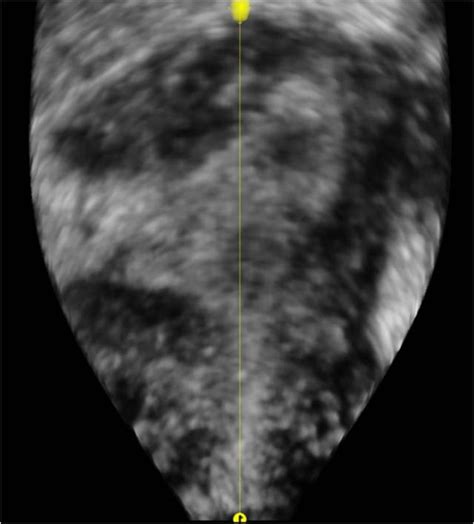

Cornual Ectopic Pregnancy

A cornual ectopic pregnancy is a rare but potentially life-threatening complication of pregnancy that requires immediate medical attention. Unlike a standard ectopic pregnancy, where the fertilized egg implants in the fallopian tube, a cornual pregnancy occurs in the cornua—the upper, lateral area of the uterus where the fallopian tube enters the uterine cavity. Because this area is highly vascular and capable of expanding slightly more than the narrow fallopian tube, these pregnancies can progress further than other types of ectopic pregnancies before they are discovered. However, this also means that when they do rupture, they can result in severe, rapid, and catastrophic hemorrhaging, making early diagnosis and prompt management essential for patient survival and reproductive health.

Diagnosing a cornual ectopic pregnancy is notoriously difficult because, in the early stages, it can appear similar to a normal intrauterine pregnancy or a standard tubal ectopic pregnancy on initial ultrasound scans. Because the cornua is part of the uterine structure, the pregnancy can remain asymptomatic longer than a tubal pregnancy, leading to a false sense of security.

• cornular ectopic pregnancy ultrasound